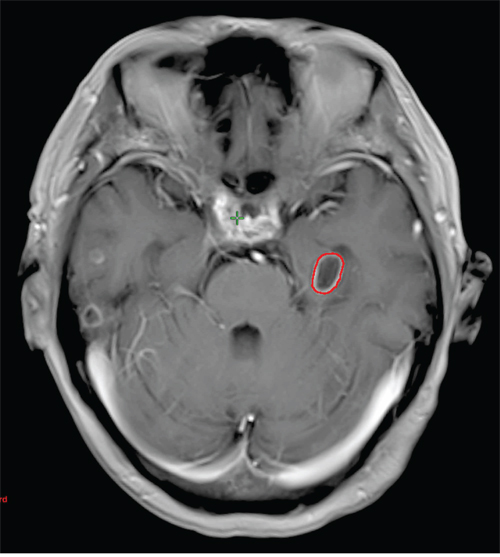

Among the 632 patients, there were 6064 metastases and the median number of metastases was 3 (range, 1–223). The distribution of metastases is shown in Table 2. The frontal lobe was the most common site of metastases (31.6%, 1919/6064), followed by parietal lobe (18.3%, 1110/6064), cerebellum (18.1%, 1098/6064), occipital lobe (13.0%, 786/6064), temporal lobe (11.7%, 708/6064) and brain stem (6.8%, 412/6064). Thirty-one metastases were within the hippocampus (0.5%, 31/6064) (Figure 1), and 37 metastases were within the peri-hippocampal region (0.6%, 37/6064). The mean hippocampus volume was 4.7 cm3 (range, 3.6–6.6 cm3). On average, hippocampal avoidance region occupied 2.1% (range, 1.7%–2.9%) of the whole brain volume (Table 3).

Figure 1: Magnetic resonance image of a patient who has a hippocampal metastasis. The red contour represents the hippocampal metastasis.